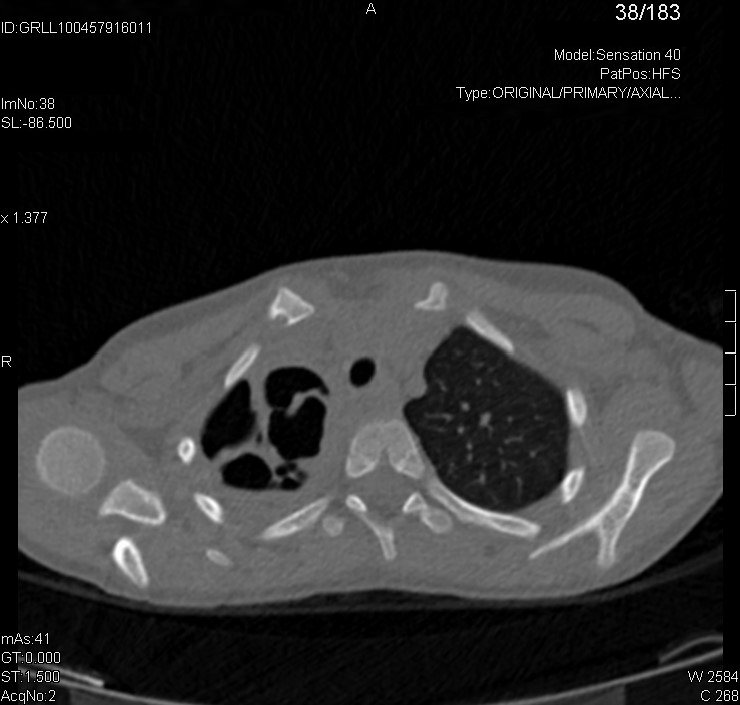

Para determinar si las imágenes de la radiografía son únicas o múltiples y definir con mayor precisión las características de las lesiones, pedimos una tomografía computarizada (TC).

La TC se informa de la siguiente manera: “En el hemitórax derecho se aprecian tres cavidades, una localizada en el lóbulo superior derecho y dos en los segmentos superiores del lóbulo inferior derecho, de paredes gruesas que no parecen estar colonizadas, sugestivas de neumonías necrotizantes. En el parénquima pulmonar izquierdo no se aprecian alteraciones significativas”.